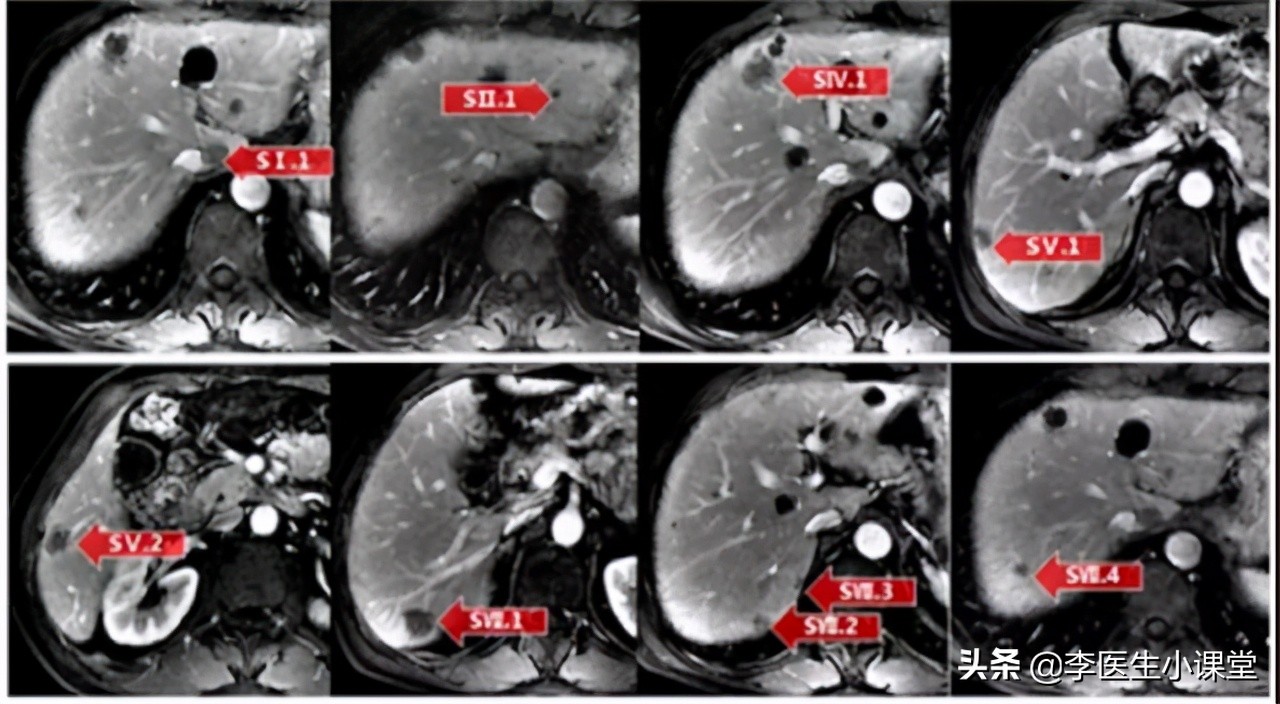

王阿姨以便血半年收入院中治疗,便 潜血试验(++++) ,这血便程度令人震惊。随后进行了肠镜检查,并取病变处进行活检。结合活检结果以及CT结果显示,王阿姨的病历如下(部分):

【肠镜显示】 :结肠肝曲面附近见 一环腔菜花样肿物,表面充血糜烂、坏死。降结肠上壁约1.3cm*1.0cm大小片状溃疡,表面糜烂坏死,肠管管腔严重狭窄。

【病理结果显示】: 距肛门40cm处为 管状腺癌 ,距肛门75cm处 癌组织呈大片或用块状排列,癌细胞大 ,胞质红染,可见细胞间桥。部分细胞质融合成片, 细胞边界不清。 有少量角化珠形成,红染,癌组织与正常肠黏膜分界清楚,间质中见 大量淋巴细胞浸润 。癌组织中未见腺样成分,肠上皮也未见鳞化。